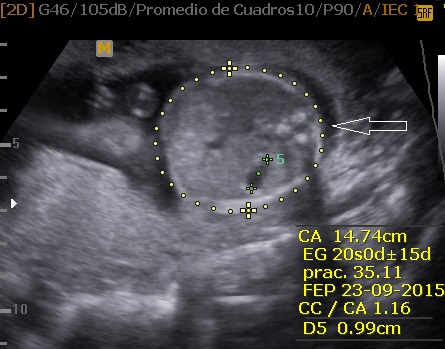

La Neurosonografía Fetal se refiere a la evaluación del Sistema Nervioso Central por Ultrasonidos: cráneo y su contenido (cerebro, ventrículos, tallo, cerebelo, etc.) y de la columna vertebral y su contenido (vértebras, médula espinal, líquido cefalorraquídeo, etc.).

Las estructuras intracraneales después de la semana 18-20 del embarazo son muy características y permanecen visualmente invariables hasta el final del embarazo, solo modificando sus tamaños a medida que el feto crece. Esto es de gran ayuda ya que permite determinar la aparición de cambios que podrían sugerir desviación de la normalidad y aparición de una malformación congénita o lesión adquirida por eventos externos especialmente relacionados a infecciones y accidentes vasculares fetales.

Cuerpo calloso: es una estructura compuesta por haces nerviosos cuya función es la de conectar e integrar regiones corticales homólogas entre ambos hemisferios cerebrales. Su ausencia total puede conducir a problemas cognitivos y del desorrollo psicomotriz o pasar totalmente desapercibida. Su ausencia parcial, paradójicamente, se asocia con peor pronóstico. Como estructura ecográfica, es una de las más bellas que hay en el cerebro pero, para obtenerla se requiere pericia y muy buena resolución ecográfica. Sus alteraciones congénitas son diagnóstico de problemas primarios del desarrollo cerebral y se manifiestan con cambios indirectos en otras secciones cerebrales, especialmente ventriculomegalia.